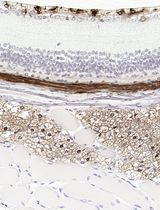

3. Optimal seeding density: A seeding density of 1.0 × 104 cells/well was identified as optimal, reliably producing a single, central spheroid per well with a uniform spherical morphology suitable for subsequent drug treatment assays (Figure 9).

Figure 9. Validation of MDA-MB-231 spheroids as a drug screening model. (A) Representative brightfield images of spheroids treated for 48 h with increasing concentrations (10, 20, 30, and 40 μM) of the chemotherapeutic agent actinomycin D. (B) Quantification of spheroid size (diameter) following treatment. Data are presented as mean ± standard deviation (SD); n = 4 biological replicates.